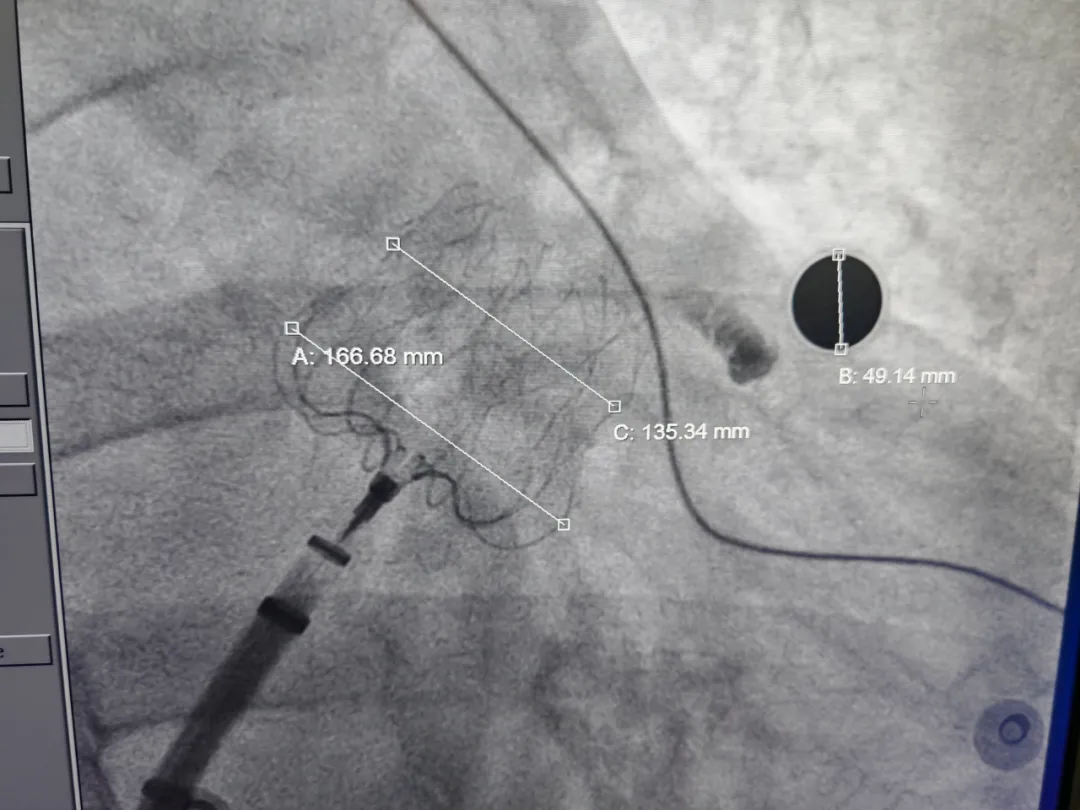

术中DSA左心耳造影测量

肝位左心耳测量,开口30.8mm,上叶深度28mm,

为大开口反鸡翅型左心耳

穿刺高低位置合适,靠下靠前

封堵器肩部锚定区无压缩,中部压缩比为19.4%

本例手术难点在于大开口反鸡翅型心耳,左心耳主叶朝向上方生长且与心耳口部成角较大,该病例左心耳存在显著解剖特殊性:心耳呈敞口形态,开口尺寸为30.8mm;远端梳状肌分布密集,同时伴随内部空间狭窄、深度28mm的特征。综合评估解剖结构与手术需求,为有效降低术后周围残余漏发生概率,本病例最终选用MemoLefort LAFDQ-32封堵器,对左心耳开口进行精准封堵。

心耳口部和体部有较大转角,鞘管轴向是关键。否则封堵器展开后容易出现露肩、弹出左心耳、无法固定等情况。术中穿刺位点靠前靠下,术中确保输送鞘轴向与左心耳轴向一致,稳步退鞘,确保封堵器释放位置合适,且牵拉稳固,术后封堵器形态完整,未见残余漏。本病例展开后即刻造影,封堵器利于倒刺结构与心耳紧密贴合,中部压缩比为19.4%,2/3覆膜率更利于配合心耳结构贴合,提高封堵效率,减少周围漏风险。为高卒中风险患者有效预防脑卒中,降低血栓风险的同时有效提升生活质量,减轻长期负担。